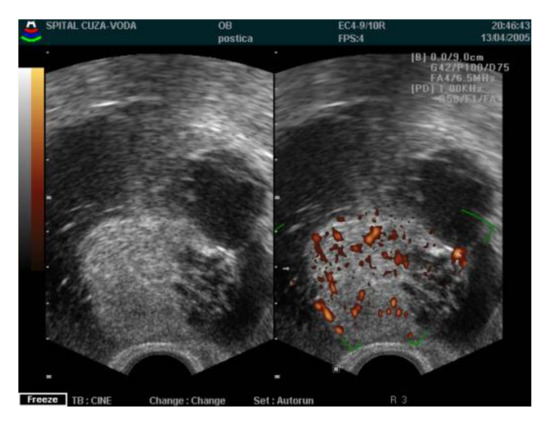

4.1. Diagnosis Approach